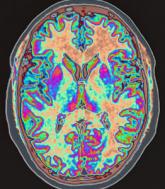

Is neuroimaging necessary to evaluate syncope?

What can I do when first-line measures are not enough for vasovagal syncope?